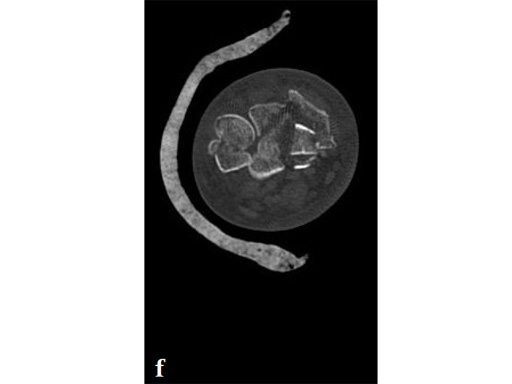

Fig 3f Ulnar head split, displaced dorsally (CT sagittal reconstruction).